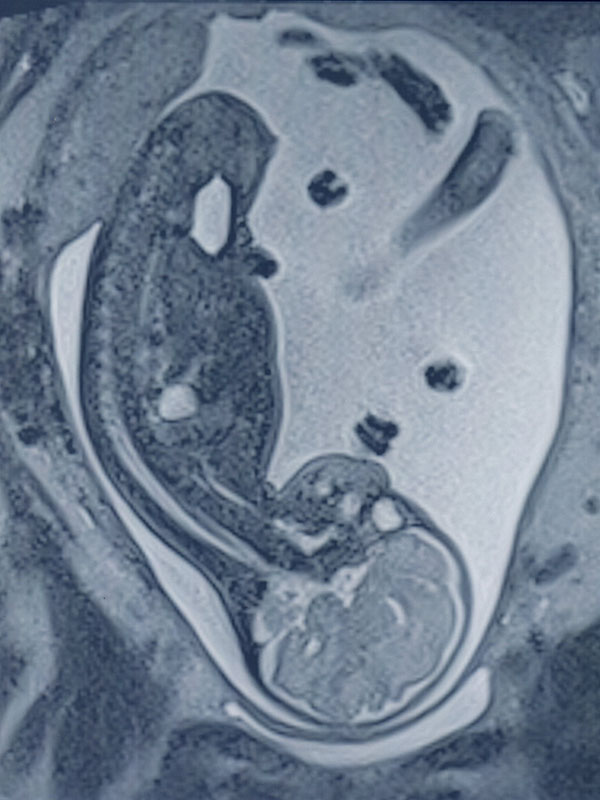

Además se realizan estudios de “Resonancia Fetal” durante el embarazo (a partir de las 12 semanas de gestación), estudios de “Mamas” con análisis anatómico – funcional y estudio de prótesis mamaria.